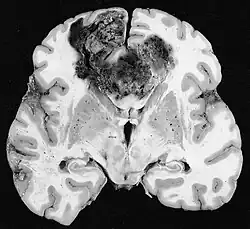

Glioblastoma

Os tumores de células gliais mais comuns e malignos são os glioblastomas. Consistem em uma massa heterogênea de células de astrocitoma pouco diferenciadas principalmente em adultos. Geralmente ocorrem nos hemisférios cerebrais, mais raramente no tronco cerebral ou na medula espinhal. Exceto em casos muito raros, como todos os tumores cerebrais, eles não se estendem além das estruturas do sistema nervoso central.

O glioblastoma pode surgir de uma forma difusa (II. grau) ou um astrocitoma anaplásico (III. grau) se desenvolvem. Neste último caso, é chamado de secundário. No entanto, quando ocorre sem antecedentes ou evidência de malignidade prévia, é referido como primário. Os glioblastomas são tratados com cirurgia, radioterapia e quimioterapia. Eles são difíceis de curar e há poucos casos que sobrevivem além de três anos.